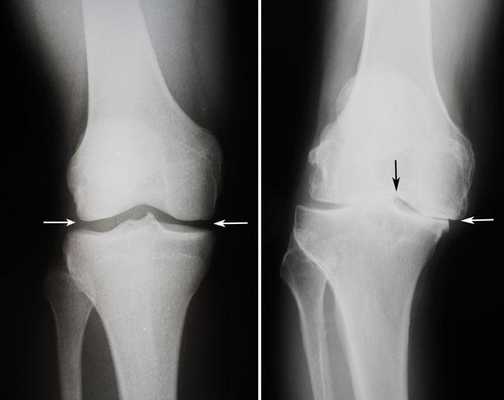

Сравнение здорового коленного сустава(слева) и полностью разрушенного(справа).

Динамика болезни на рентгене.